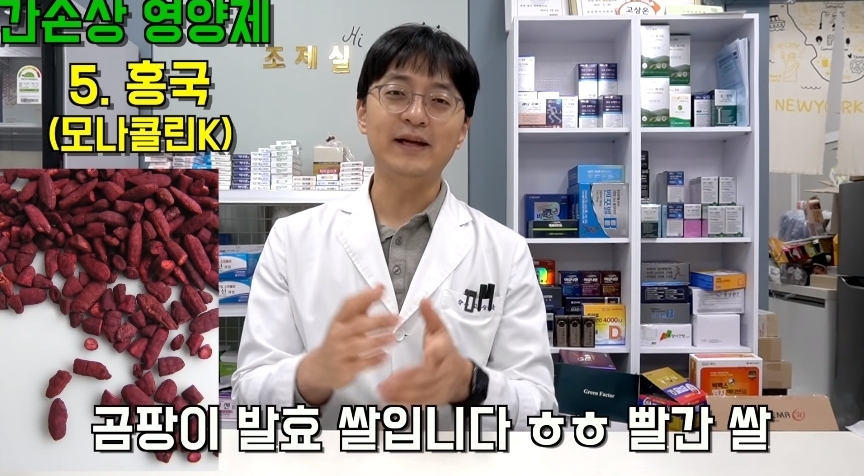

그러나 한번만 먹어도 간이 망가질 수 있다는 영양제들에 대한 글이 온라인 커뮤니티에 올라와 누리꾼들 사이에서 엄청나게 화제가 되고 있다.

해당 게시물에는 먹으면 오히려 몸에 안좋은 영양제들이 올라왔다.